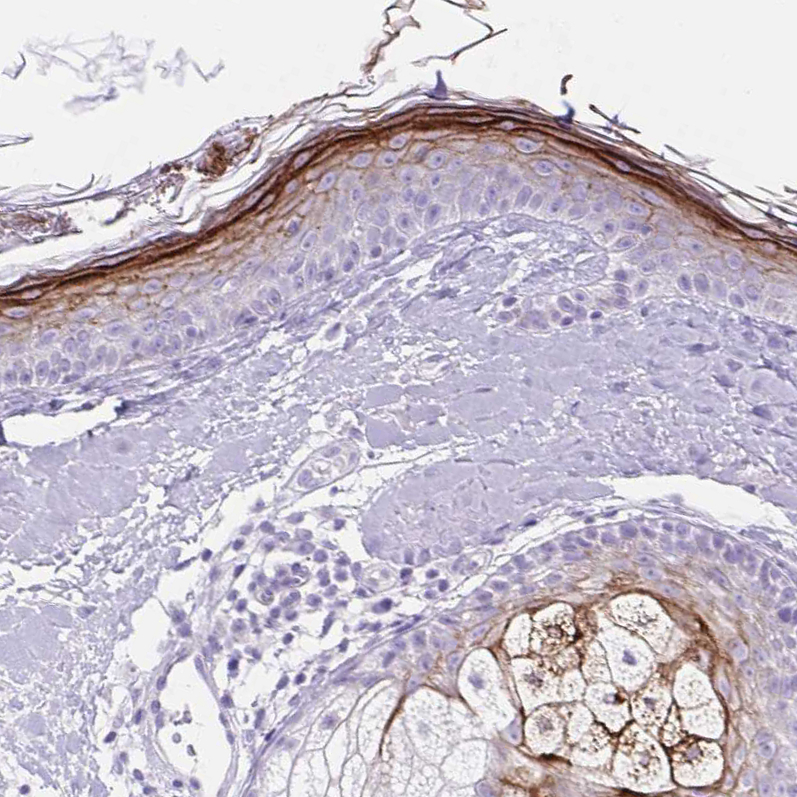

Immunohistochemistry analysis in human skin and pancreas tissues using HPA054184 antibody. Corresponding CDSN RNA-seq data are presented for the same tissues.